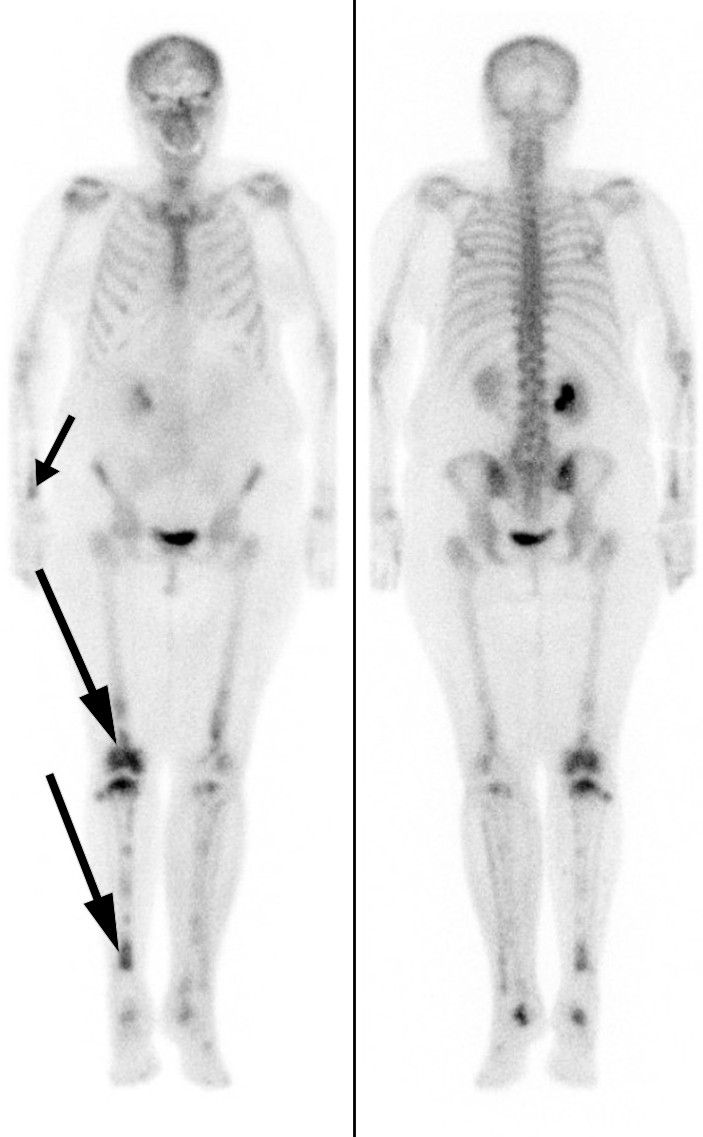

CT abdomen-bildene ble oversendt til et universitetssykehus for ny vurdering. Radiologen bemerket påfallende forandringer rundt nyrene (fig 1) – et funn som tydet på såkalte hårete nyrer (hairy kidneys). Pasienten ble overført til universitetssykehuset for videre utredning.

Hårete nyrer er uttrykk for retroperitoneal fibrose som infiltrerer perirenalt fettvev, med fortykkelse av nyrekapslene. Ved funn av retroperitoneal fibrose er den som regel lokalisert rundt abdominalaorta og iliaca communis-karene, men den kan også være mer utbredt (9). Retroperitoneal fibrose er i over 70 % av tilfellene idiopatisk (10), mens de resterende kan skyldes for eksempel medikamenter, malignitet, infeksjoner, kirurgi, stråling, amyloidose og histiocytoser (9). Idiopatisk retroperitoneal fibrose klassifiseres ofte som en kronisk periaortitt, enten isolert eller assosiert med andre autoimmune sykdommer eller immunglobulin G4 (IgG4)-relatert sykdom (11). Symptomene kan være vage og lite spesifikke. Det typiske er korsryggssmerter, eventuelt med utstråling til lysken, ledsaget av vekttap, redusert appetitt, utmattelse, feber, oppkast og kvalme. Ikke rent sjelden – som hos vår pasient – oppdages tilstanden tilfeldig når abdomen undersøkes radiologisk. Men i vårt tilfelle var infiltrasjonen mer utbredt enn det som er vanlig ved retroperitoneal fibrose.

Symmetrisk osteosklerose i diafysene og metafysene i lange rørknokler, inflammatoriske forandringer rundt aorta (coated aorta) og perirenal infiltrasjon av histiocytter (hårete nyrer) er typiske radiologiske funn (25, 28, 29). Sistnevnte er nærmest patognomonisk for tilstanden og en viktig grunn til at diagnosen tidlig ble mistenkt hos vår pasient. Det histologiske bildet er karakterisert av lipidfylte såkalte skumhistiocytter, ofte kombinert med fibrose. Immunhistokjemisk vil de være positive for CD68, CD163 og faktor XIIIa, og i noen tilfeller for S100, som skiller dem fra histiocytter ved en del andre tilstander. De vil også være negative for CD1a og langerin (CD207) (27).